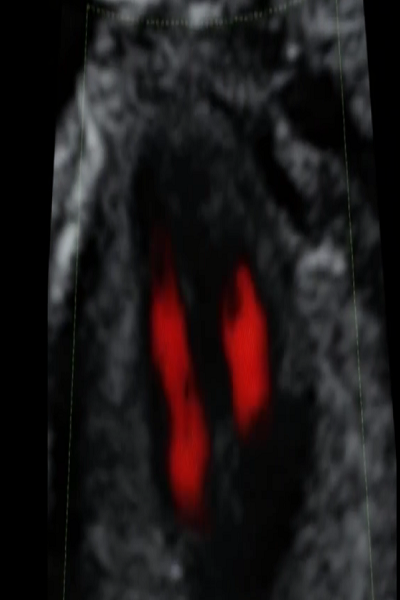

产科超声-胎儿早期评价